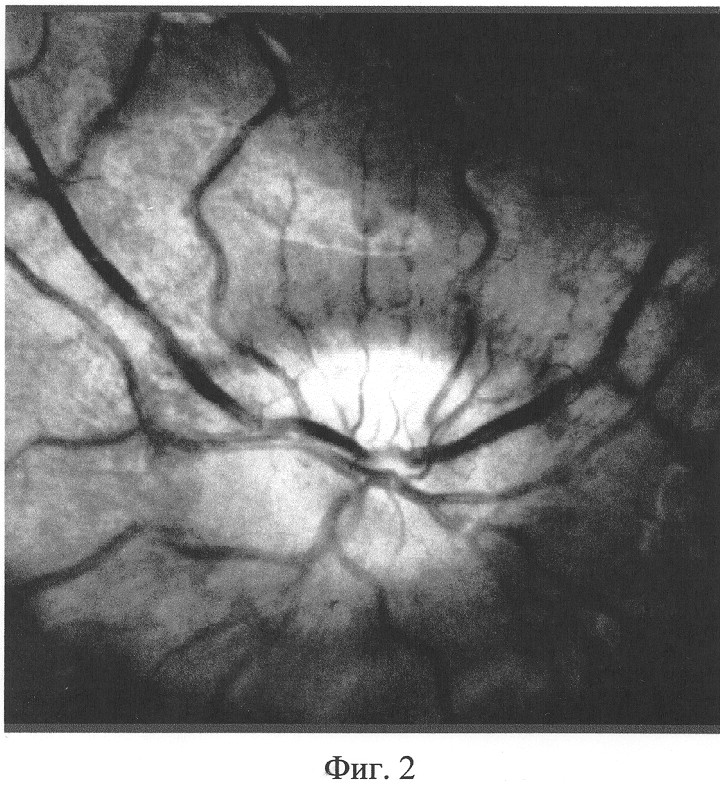

На Фиг.2 приведено обработанное изображение выделенной на Фиг.1 области для одной из выделенных точек интереса (распределение степени корреляции цвета точки А со всеми остальными точками исходного изображения). Доля площади с максимальной яркостью показана на диаграмме Фиг.3.

Аналогичную процедуру проводят с изображением в процессе и после лечения. На Фиг.4 приведено изображение той же области зрительного нерва после лечения. По предложенным выше этапам обрабатывается изображение. На Фиг.5 сформировано новое изображение, на котором определена доля площади с максимальной яркостью (диаграмма на Фиг.6). Сравнивают эти площади и проводят мониторинг динамики лечения патологии зрительного нерва.

Изображение глазного дна пациента Ф. было получено с помощью фундус-камеры фирмы TOPCON (Япония) и цифрового аппарата Nikon. Фиг.7. Проведена обработка данного изображения по предложенному способу, где нас интересовала исходная площадь отека тканей глазного дна. Фиг.8. Составлена диаграмма отношения общей площади, к площади отека. Фиг 9. Доля площади отека до лечения составила 46%.